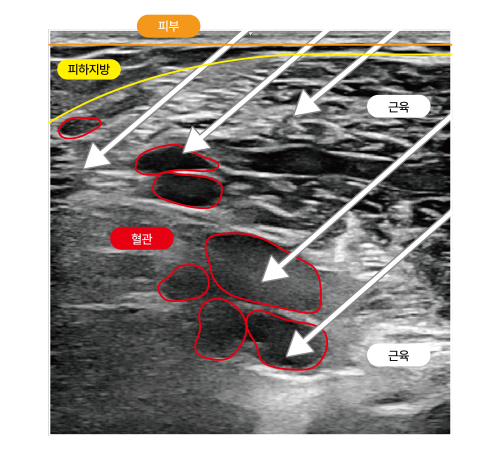

초음파 정밀분석으로 근육의 깊이·형태·혈관 분포를 실시간으로 파악하며,

근육의 깊이·형태·혈관 분포를 초음파로 정밀하게 육안으로 확인하고,

초음파로 근육, 혈관 실시간 모니터링

근육과 혈관 구조를 실시간으로 확인, 안전하고 정확한 시술 설계